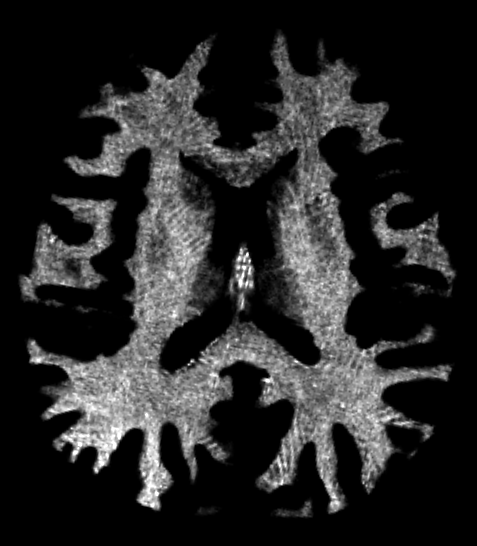

Were these three factors underpinned by three brain circuits? Different circuits did indeed seem to be involved when the Canadian team did a follow-up study of 16 people with a $5 million fMRI scanner. In a way we had distilled intelligence into fractions.

In collaboration with Hampshire, they went on to show the power of the Automatic Neuroscientist with a pilot brain imaging study on 21 volunteers from their lab who performed 16 different cognitive tasks. The machine was asked to find which brain circuits were activated by each task, including some from the 2012 Neuron paper.

Two tasks cleanly harnessed independent circuits, both from the 2012 paper: Deductive Reasoning, when subjects have to spot the ‘odd one out’, and the Tower of London task, where they are shown a tree-like frame festooned with numbered beads, then asked to put the beads in the right order. Confirmation of two of the three circuits identified by the 2012 paper was encouraging but, as Hampshire says, probably “sheer, blind, luck.”